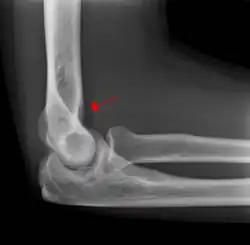

The fat pad sign, also known as the sail sign, is a potential finding on elbow radiography which suggests a fracture of one or more bones at the elbow. It may indicate an occult fracture that is not directly visible. Its name derives from the fact that it has the shape of a spinnaker (sail).[1] It is caused by displacement of the fat pad around the elbow joint. Both anterior and posterior fat pad signs exist, and both can be found on the same X-ray.

In addition to fracture, any process resulting in an elbow joint effusion may also demonstrate an abnormal fat pad sign. Increased intracapsular fluid is also seen in several conditions other than fracture and this produces the abnormal fat pad sign. (toxic synovitis, septic arthritis, Juvenile Rheumatoid Arthritis, osteomyelitis of the distal humeral physis and secondary septic joint). In these instances, history and clinical examination in addition laboratory results (WBC, ESR, CRP) will guide the provider in determining whether to treat the condition as an occult fracture or continue workup for other pathology.

The posterior fat pad is normally pressed in the olecranon fossa by the triceps tendon, and hence invisible on lateral radiograph of the elbow.[3] When there is a fracture of the distal humerus, or other pathology involving the elbow joint, inflammation develops around the synovial membrane forcing the fat pad out of its normal physiologic resting place. This is visible as the "posterior fat pad sign" and is often the only visible marker of a fracture, particularly in the pediatrics population.